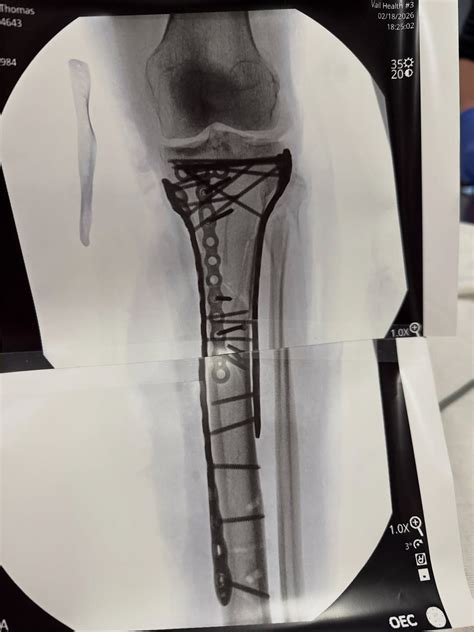

Cicatrici Visibili, Forza Interiore

Il viso di Lindsey Vonn tradisce la sofferenza e la preoccupazione, ma il suo calvario è raccontato quotidianamente sui social media con una dignità e una grinta ammirevoli, infondendo coraggio anche a se stessa. "Ho superato l'operazione, ci sono volute oltre sei ore per concluderla. Come potete vedere sono serviti tante viti e placche per rimettere insieme tutto," ha dichiarato, mostrando un grande peluche abbracciato sul letto d'ospedale.

Lindsey Vonn continua ad aggiornare i suoi numerosi tifosi, in apprensione dopo la terribile caduta a Cortina. L'8 febbraio, le sono state diagnosticate fratture multiple alla gamba e al femore. Dopo essere stata operata quattro volte all'ospedale di Treviso, è stata trasferita negli Stati Uniti, dove ha subito un quinto intervento. "Il dottor Hackett ha fatto un lavoro incredibile," ha scritto Vonn, postando video e foto delle radiografie della sua gamba. "Vista l'entità del trauma ho avuto qualche difficoltà nel post operatorio e non sono riuscita ancora ad essere dimessa dall'ospedale. Ci siamo quasi, a piccoli passi."